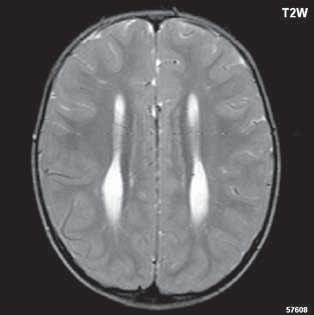

Roztroušená skleróza (RS) 189

II 1 1